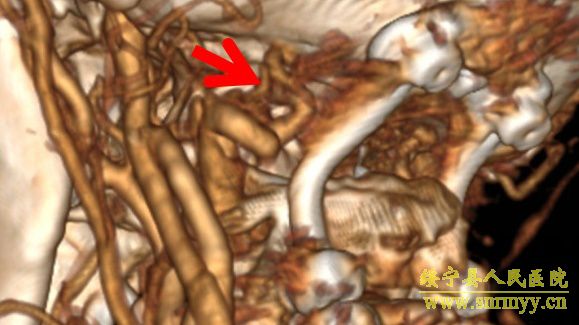

9月2日,我院神经外科在解放军昆明总医院封亚平教授的指导下,成功实施县内首台上颈椎、颅颈交接区手术,这标志着我院神经外科诊疗技术又迈上了一个新台阶。 40岁女性患者,因“头疼头晕伴左侧肢体麻木3年余,加重1月”入院,诊断为环枕畸形合并小脑扁桃体下疝。MRI及CT显示:枕颈融合,寰枢关节脱位,颅底陷入,颅颈角明显变小,小脑扁桃体下疝、延颈交界脊髓明显受压(如图下图所示),此病的症结是那块骨头(红色箭头处)压迫了神经! 想要解决问题,自然就得把那块骨头“掰”下来。骨头虽小,真要把它“掰”下来却绝非易事,需要把颈1-2的小关节撑开,但是,患者的小关节后面还有很粗大的动脉血管(蓝色箭头)挡着,手术难度相当大! 经解放军昆明总医院封亚平教授会诊,我院神经外科为该患者实施了后入路枕骨大孔区减压、寰枢椎脱位复位、枕颈固定、植骨融合术,手术用时短短1.5小时,出血量仅50ml。病人术后神经压迫症状明显改善,第一天开始进食,第二天即可下床活动。 (斜坡颈椎角增大到正常) (术后复查CT及MRI显示寰枢关节脱位复位理想,颅颈角增大基本正常,脊髓受压解除。) (术中无血管、神经损伤) 寰枕畸形是枕骨大孔区、寰枢椎骨质发育异常伴神经系统、椎动脉及附近软组织发育异常的一种先天性畸形疾病。寰枕畸形主要包:扁平颅底、颅底凹陷、寰枕融合、颈椎分节不全、寰枢椎脱位、小脑扁桃体下疝畸形。寰枕畸形可继发于畸形性骨炎、软骨病、佝偻病等。寰枕畸形患者早期临床表现为颈短、头颈痛、活动受限等。对于颈部粗而短的人群而言,寰枕畸形的发病可能相较一般人更高。原因在于,颈部粗短的人在转头活动的过程中,关节的活动度比较大,磨损的程度也更高,因而更容易发病。寰枕畸形合并小脑扁桃体下疝及脊髓空洞症为先天性发育不良所致,成年起病,无任何药物可治疗,手术是唯一有效的治疗办法。起初,患者会逐渐出现颈肩部疼痛,手臂麻木、无力,行走不稳等症。若不及时治疗,晚期预后会很差。(图为 邓泽亮 编辑 雅玲) 神经外科电话0739-2570859 科主任邓泽亮13975968148 副主任黄敏15211991811 |